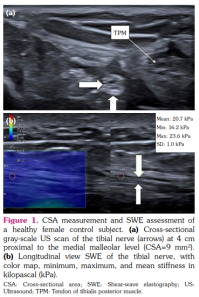

Tibial nerve was examined in the transverse and longitudinal planes at a distance of 4 cm proximal to the tip of the medial malleolus. The correct imaging plane was confirmed by tendinous landmarks, such as the flexor digitorum longus and flexor hallucis longus tendons, and the posterior tibial vessels.[16] CSA was measured by the use of a continuous boundary trace of the nerve directly over the epineurium on transverse images (Figures 1, 2).

Shear-wave elastography was performed by careful handling of the transducer during transport and mounting to avoid compression force. The skin surface was coated with ample coupling gel before placing the transducer, which was used with light force and kept stable during image acquisition. TN was first identified transversely, and then the transducer was rotated 90° to acquire a longitudinal image of the nerve in the parallel direction to the fiber orientation.[16]